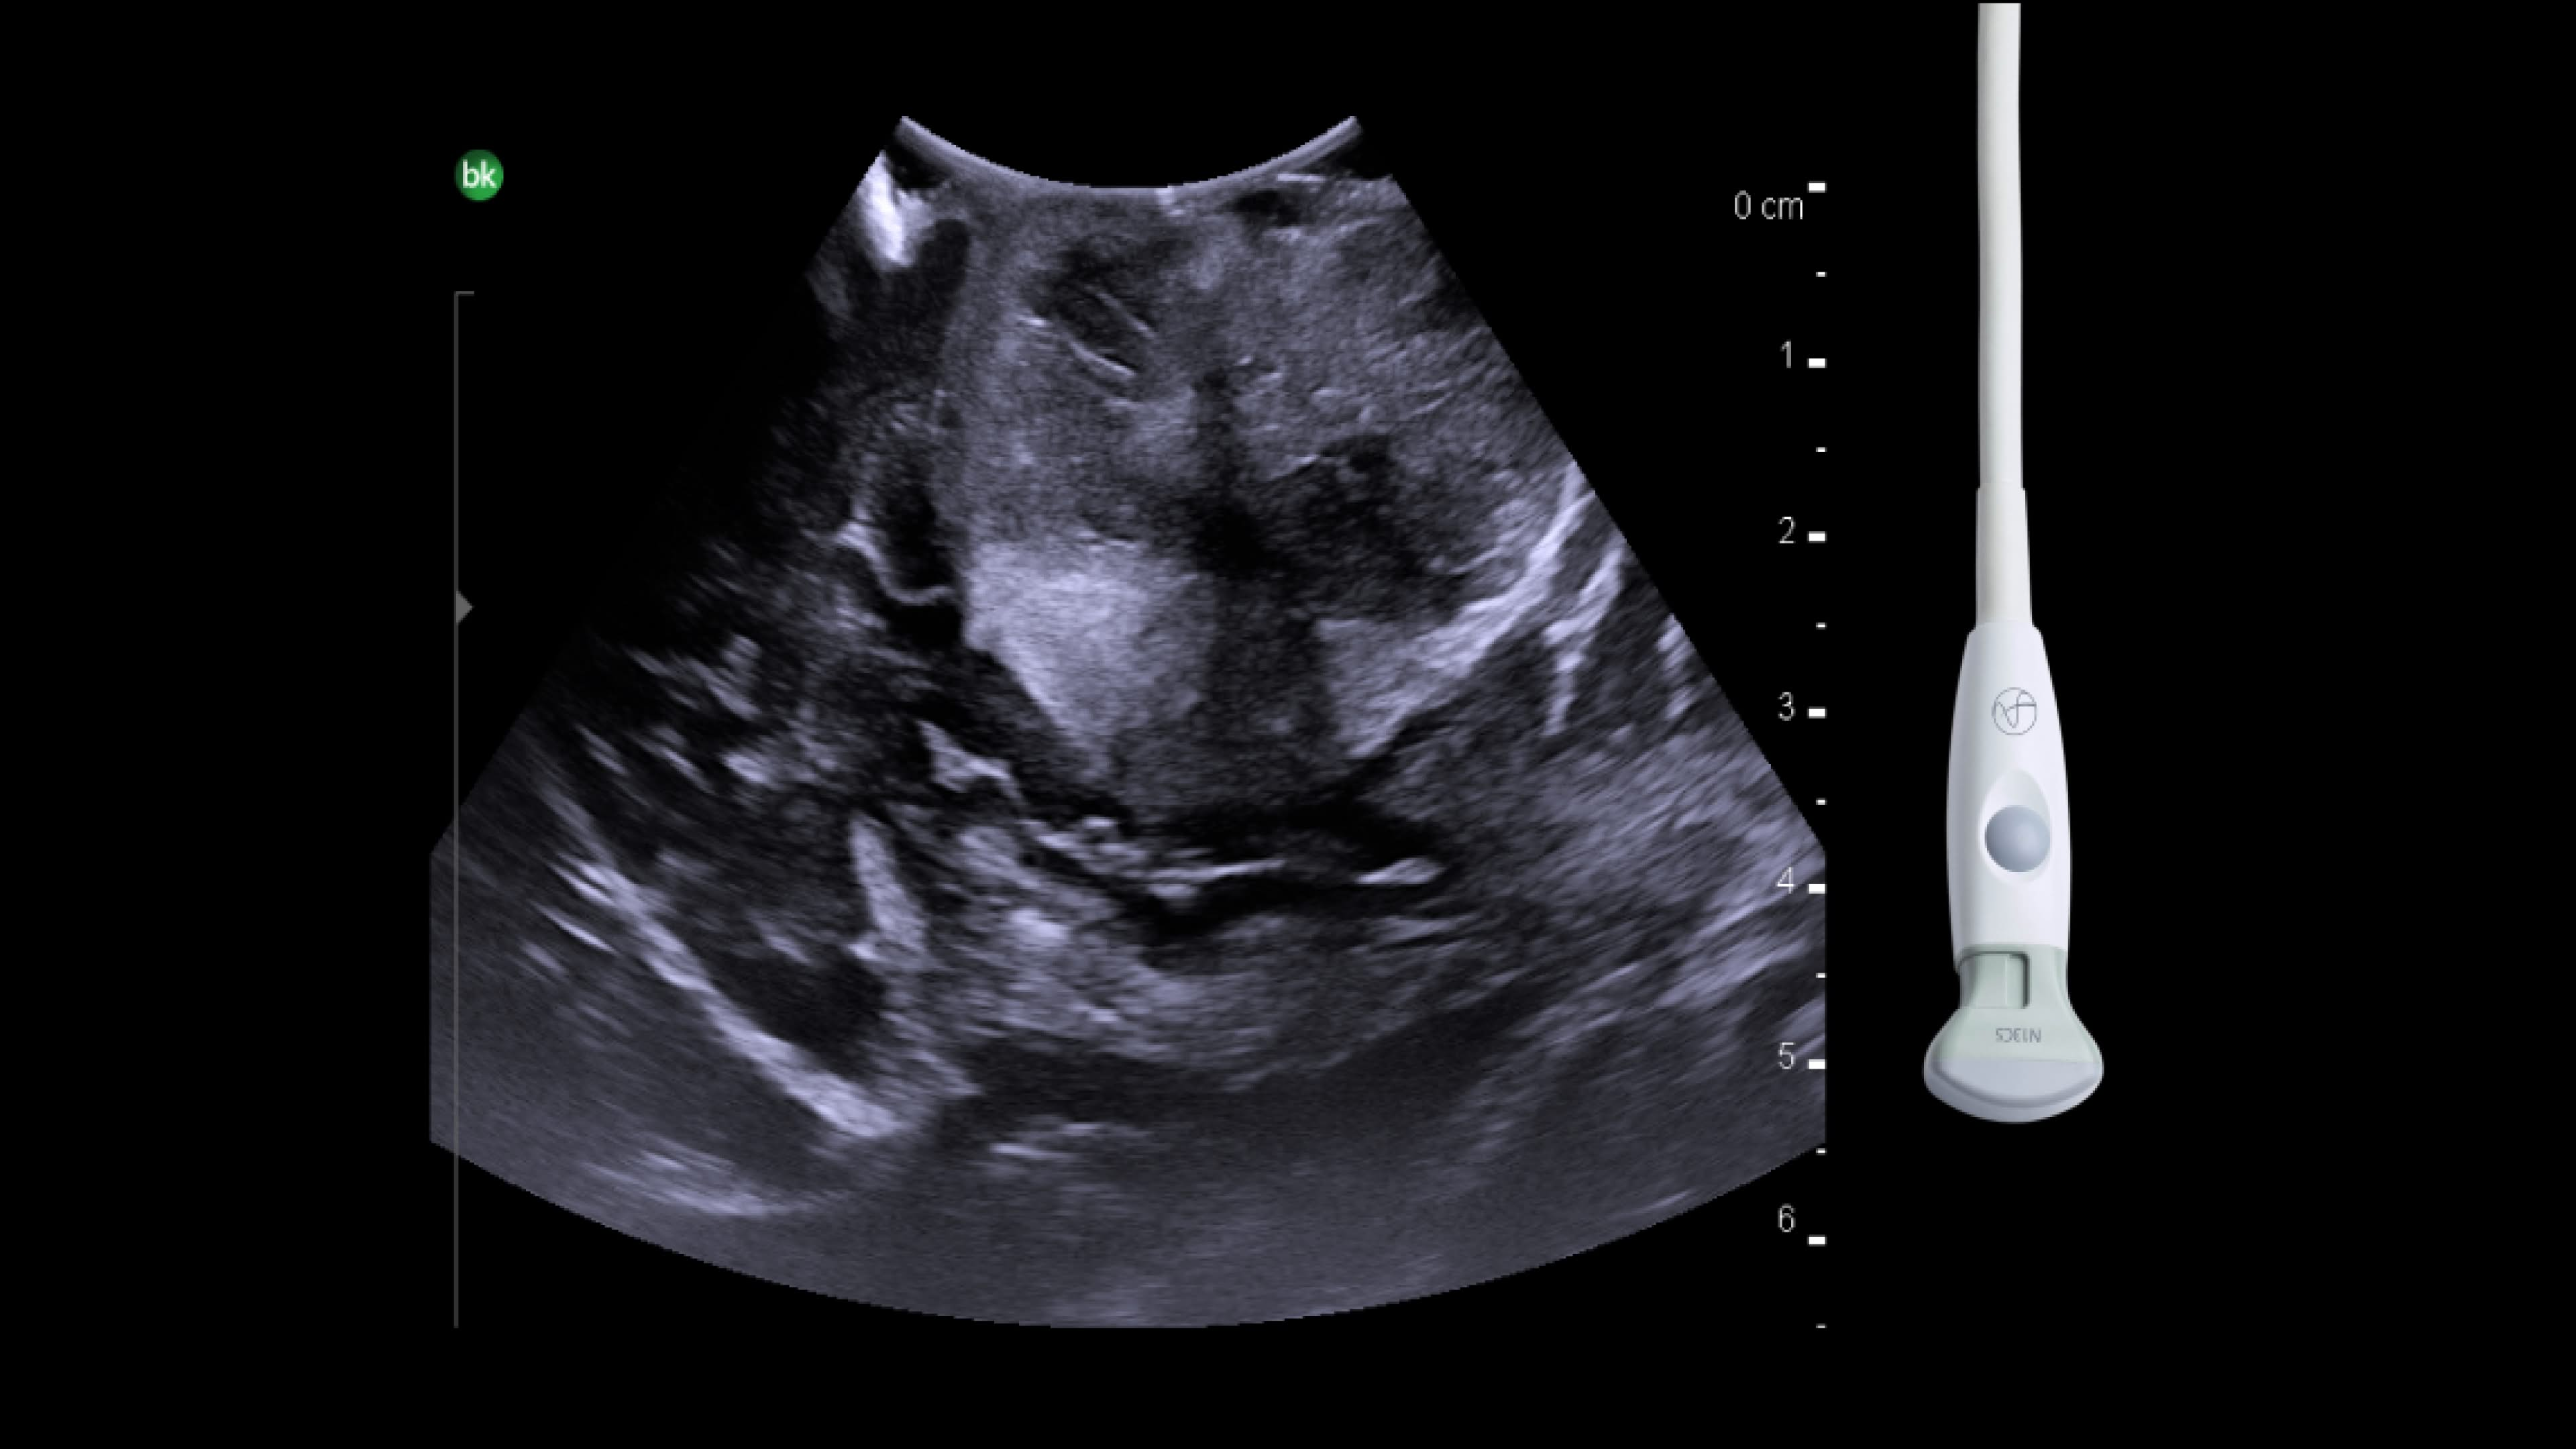

Neuro-oncology

Use intraoperative ultrasound during surgery to assist in the identification of brain shift after pre-operative scans and determine extent of resection and assess for residual tumor.